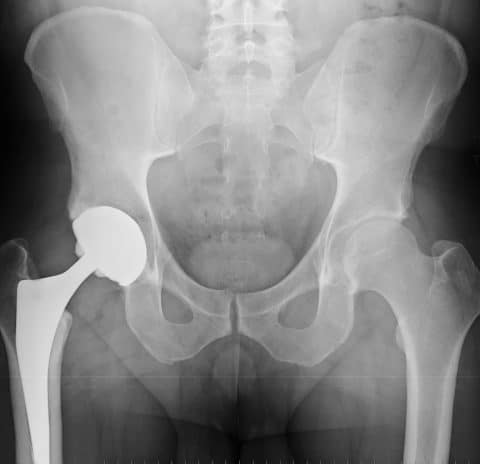

The modular versions of the SMF, originally approved and marketed as the MIS Hip Stem in 2008, and REDAPT Revision implant, approved by the FDA in 2012, each have cobalt and chromium neck pieces that fit into titanium stems.

In some cases, the friction of the metal-on-metal components rubbing against each other can cause metal ions in the components to rub off and be absorbed into the body, potentially causing serious medical complications.(4)